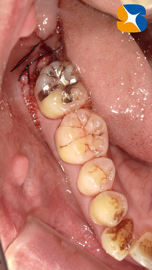

レントゲンからも大きな虫歯を確認。本日、昼休み中にインプラント手術があります。それが終わり次第抜歯を行うことにしました。

歯の上半分が虫歯のため、崩壊していましたので難しい抜歯になりましたが、無事に終えることができました。